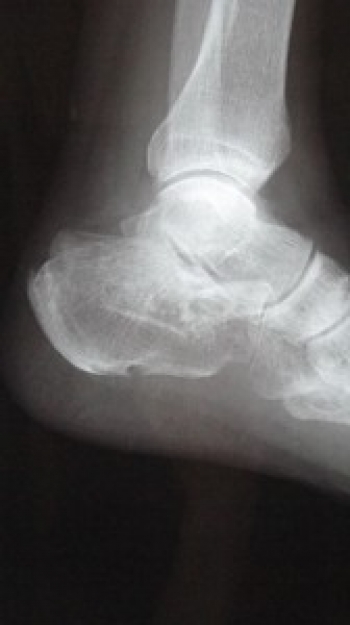

踵骨骨折

踵骨は足根骨の中で最大の骨で、歩行時に最初に接地する部位に位置し、足根骨骨折中もっとも頻度が高い。

距骨などと複雑な形態の関節面を有するため、骨折が生じると関節内骨折を起こしやすい。

分類は、関節外骨折、関節内骨折がある。